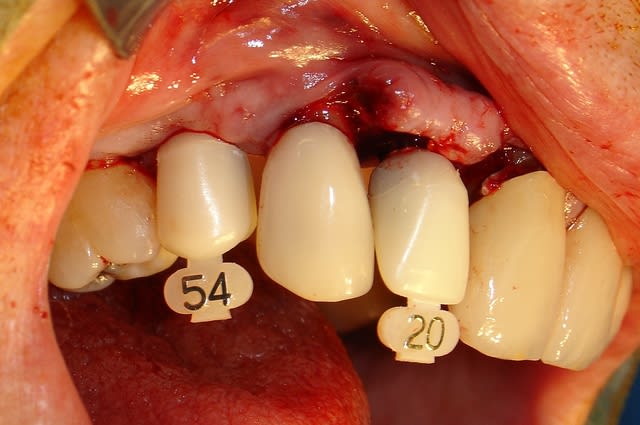

Je l'ai essayé aussi hier. Une MCI à l'arrache ext implantation sur 14 en remplacement d'un bridge en extension sur 12. Je ne suis pas trop mécontent du résultat puisque sans aucune préparation quasiment et sans scan.

Un 3.2 en 12 et un 3.7 en 14.

Très bonne accroche, facile de corriger les FM et provisoire facilement réalisable à main levée.

Etant donné que je ne transvisse pas et que je n'utilise que l'ajustage pour la tenue des provisoires je trouve qu'il est super pratique.